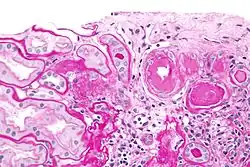

| Micrograph showing renal arterial hyalinosis – pink ring right-of-centre. PAS stain. | |

In benign nephrosclerosis, the changes occurring are gradual and progressive, however, there can be sufficient kidney reserve capacity to maintain adequate kidney function for many years.[10] The large renal arteries exhibit intimal thickening, medial hypertrophy, duplication of the elastic layer. The changes in small arterioles include hyaline arteriolosclerosis (deposition of hyaline, collagenous material), which causes glomerular collapse (wrinkling and thickening of capillary basement membranes and collapse of capillary lumen) and solidification (glomeruli exhibit sclerosis and increase in mesangial matrix). The degree of scarring correlates with the degree of glomerular filtration deficit.